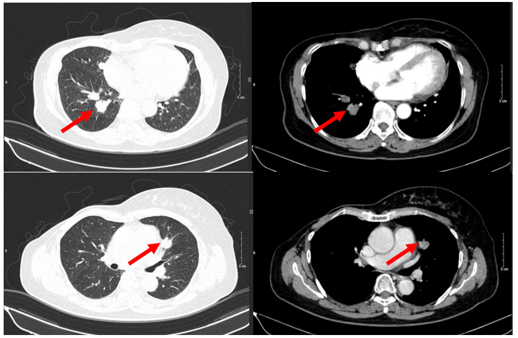

- Chụp cắt lớp vi tính ngực:

+ Thành ngực phải có nốt đặc đường kính 5mm – theo dõi tổn thương tái phát

Phổi phải: nhu mô thuỳ giữa và dưới có các khối – nốt đặc, lớn nhất 7x8mm

+ Phổi trái: nhu mô thuỳ trên và đáy phổi sát màng phổi có các khối nốt đặc, lớn nhất 9x8mm

Hình 8. Hình ảnh chụp CT ngực sau điều trị: Tổn thương tái phát thành ngực

Hình 9. Hình ảnh chụp CT ngực sau điều trị: Tổn thương phổi 2 bên